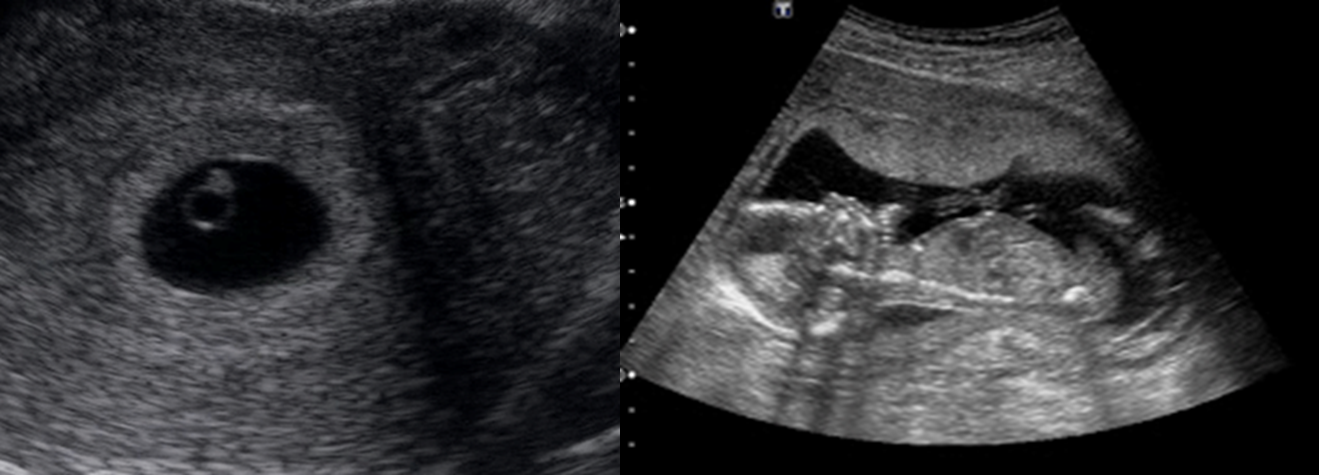

Confirm viable pregnancy: Gestational Sac (GS):

- Visible at 4-5wks GA with transvaginal US

- Visible at 6 wks GA with transabdominal US

- GS: echogenic ring with anechoic center within uterine cavity

- Measure by Mean Sac Diameter: average dimensions of width/length/height of sac

Considerations Ultrasound findings in normal pregnancy:

- In an intrauterine pregnancy at 5–6 weeks’ gestation, a gestational sac and yolk sac are visible in the uterus.